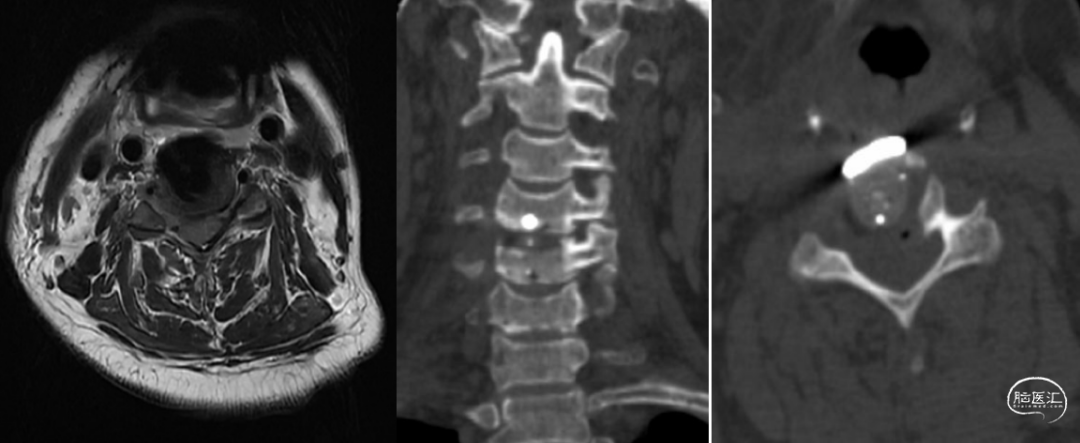

术前颈椎磁共振复查提示:颈3/4、颈4/5椎间盘突出,颈5/6、颈6/7椎间盘膨出,颈4/5椎间盘水平受压脊髓轻度变性(图1)。颈椎CT提示:颈椎退行性变,C4-5椎体右侧钩椎关节增生(图2)。

手术方案拟采用“[颈4-5]颈前路椎管减压术+植骨融合内固定术”。因C5神经根支配区域受累明显,颈椎CT提示C4-5椎体右侧椎间孔明显狭窄,右侧钩椎关节增生明显,且MRI提示C4/5椎间盘水平脊髓可见变性,拟术中联合切除右侧钩椎关节以获得颈5神经根充分减压。

患者麻醉实施成功后取仰卧位,头略转向左侧,颈部术野常规消毒、铺巾。作右颈前横切口长约4cm,逐层切开皮肤、皮下组织、颈阔肌,自胸锁乳突肌内侧钝性分离,分离直达颈椎前方。经C形臂影像增强器透视确定C4椎体,剥离椎前筋膜和前纵韧带,显露椎体前方,于C4/C5椎体上各置入撑开螺钉1枚,撑开器适当撑开,彻底清除C4/5椎间盘,暴露至椎体后缘,切除右侧钩椎关节,硬膜囊及右侧颈5神经根彻底减压(图3)。

术后颈椎CT及磁共振显示右侧颈4/5钩椎关节切除,右侧椎间孔较术前明显扩大(图4)。